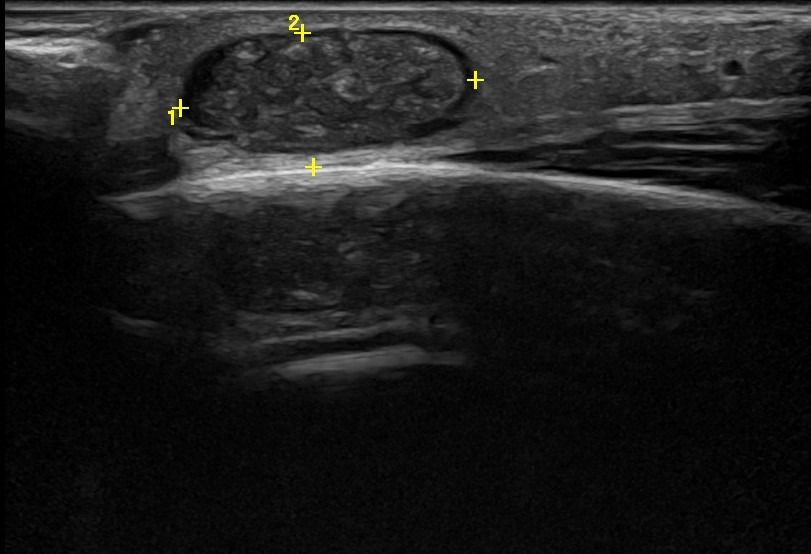

Η τεχνική του Έγχρωμου Doppler μελετάει την αγγείωση της βλάβης. Η τεχνική του Παλμικού Doppler μελετάει την παρουσία αρτηριακών ή φλεβικών στοιχείων εντός της βλάβης. Επίσης πολύ χρήσιμη είναι η Ελαστογραφική Μελέτη η οποία μελετάει τη σκληρότητας της βλάβης. Οι τεχνικές αυτές μας βοηθούν να χαρακτηρίσουμε αν η βλάβη είναι αγγειακού τύπου και αν έχει καλοήθη η ύποπτα χαρακτηριστικά.